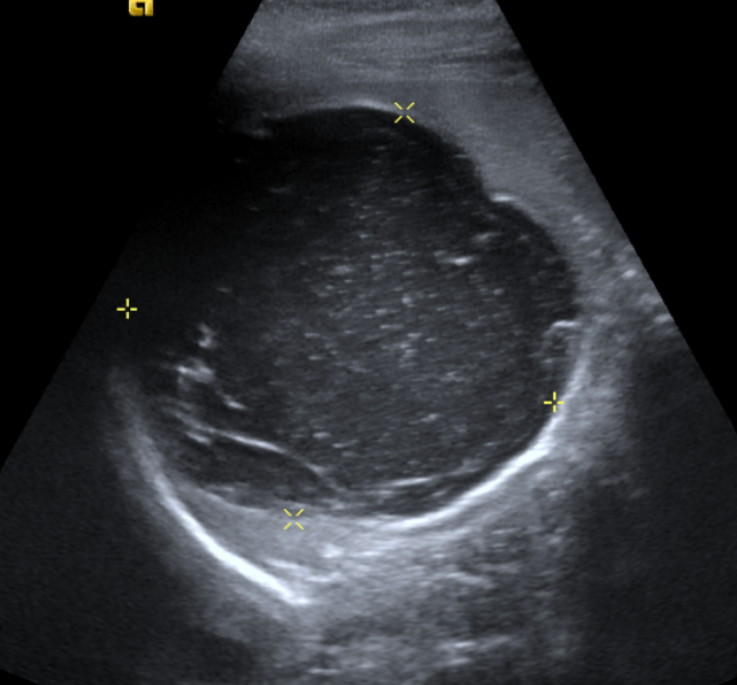

Hallazgos radiológicos: